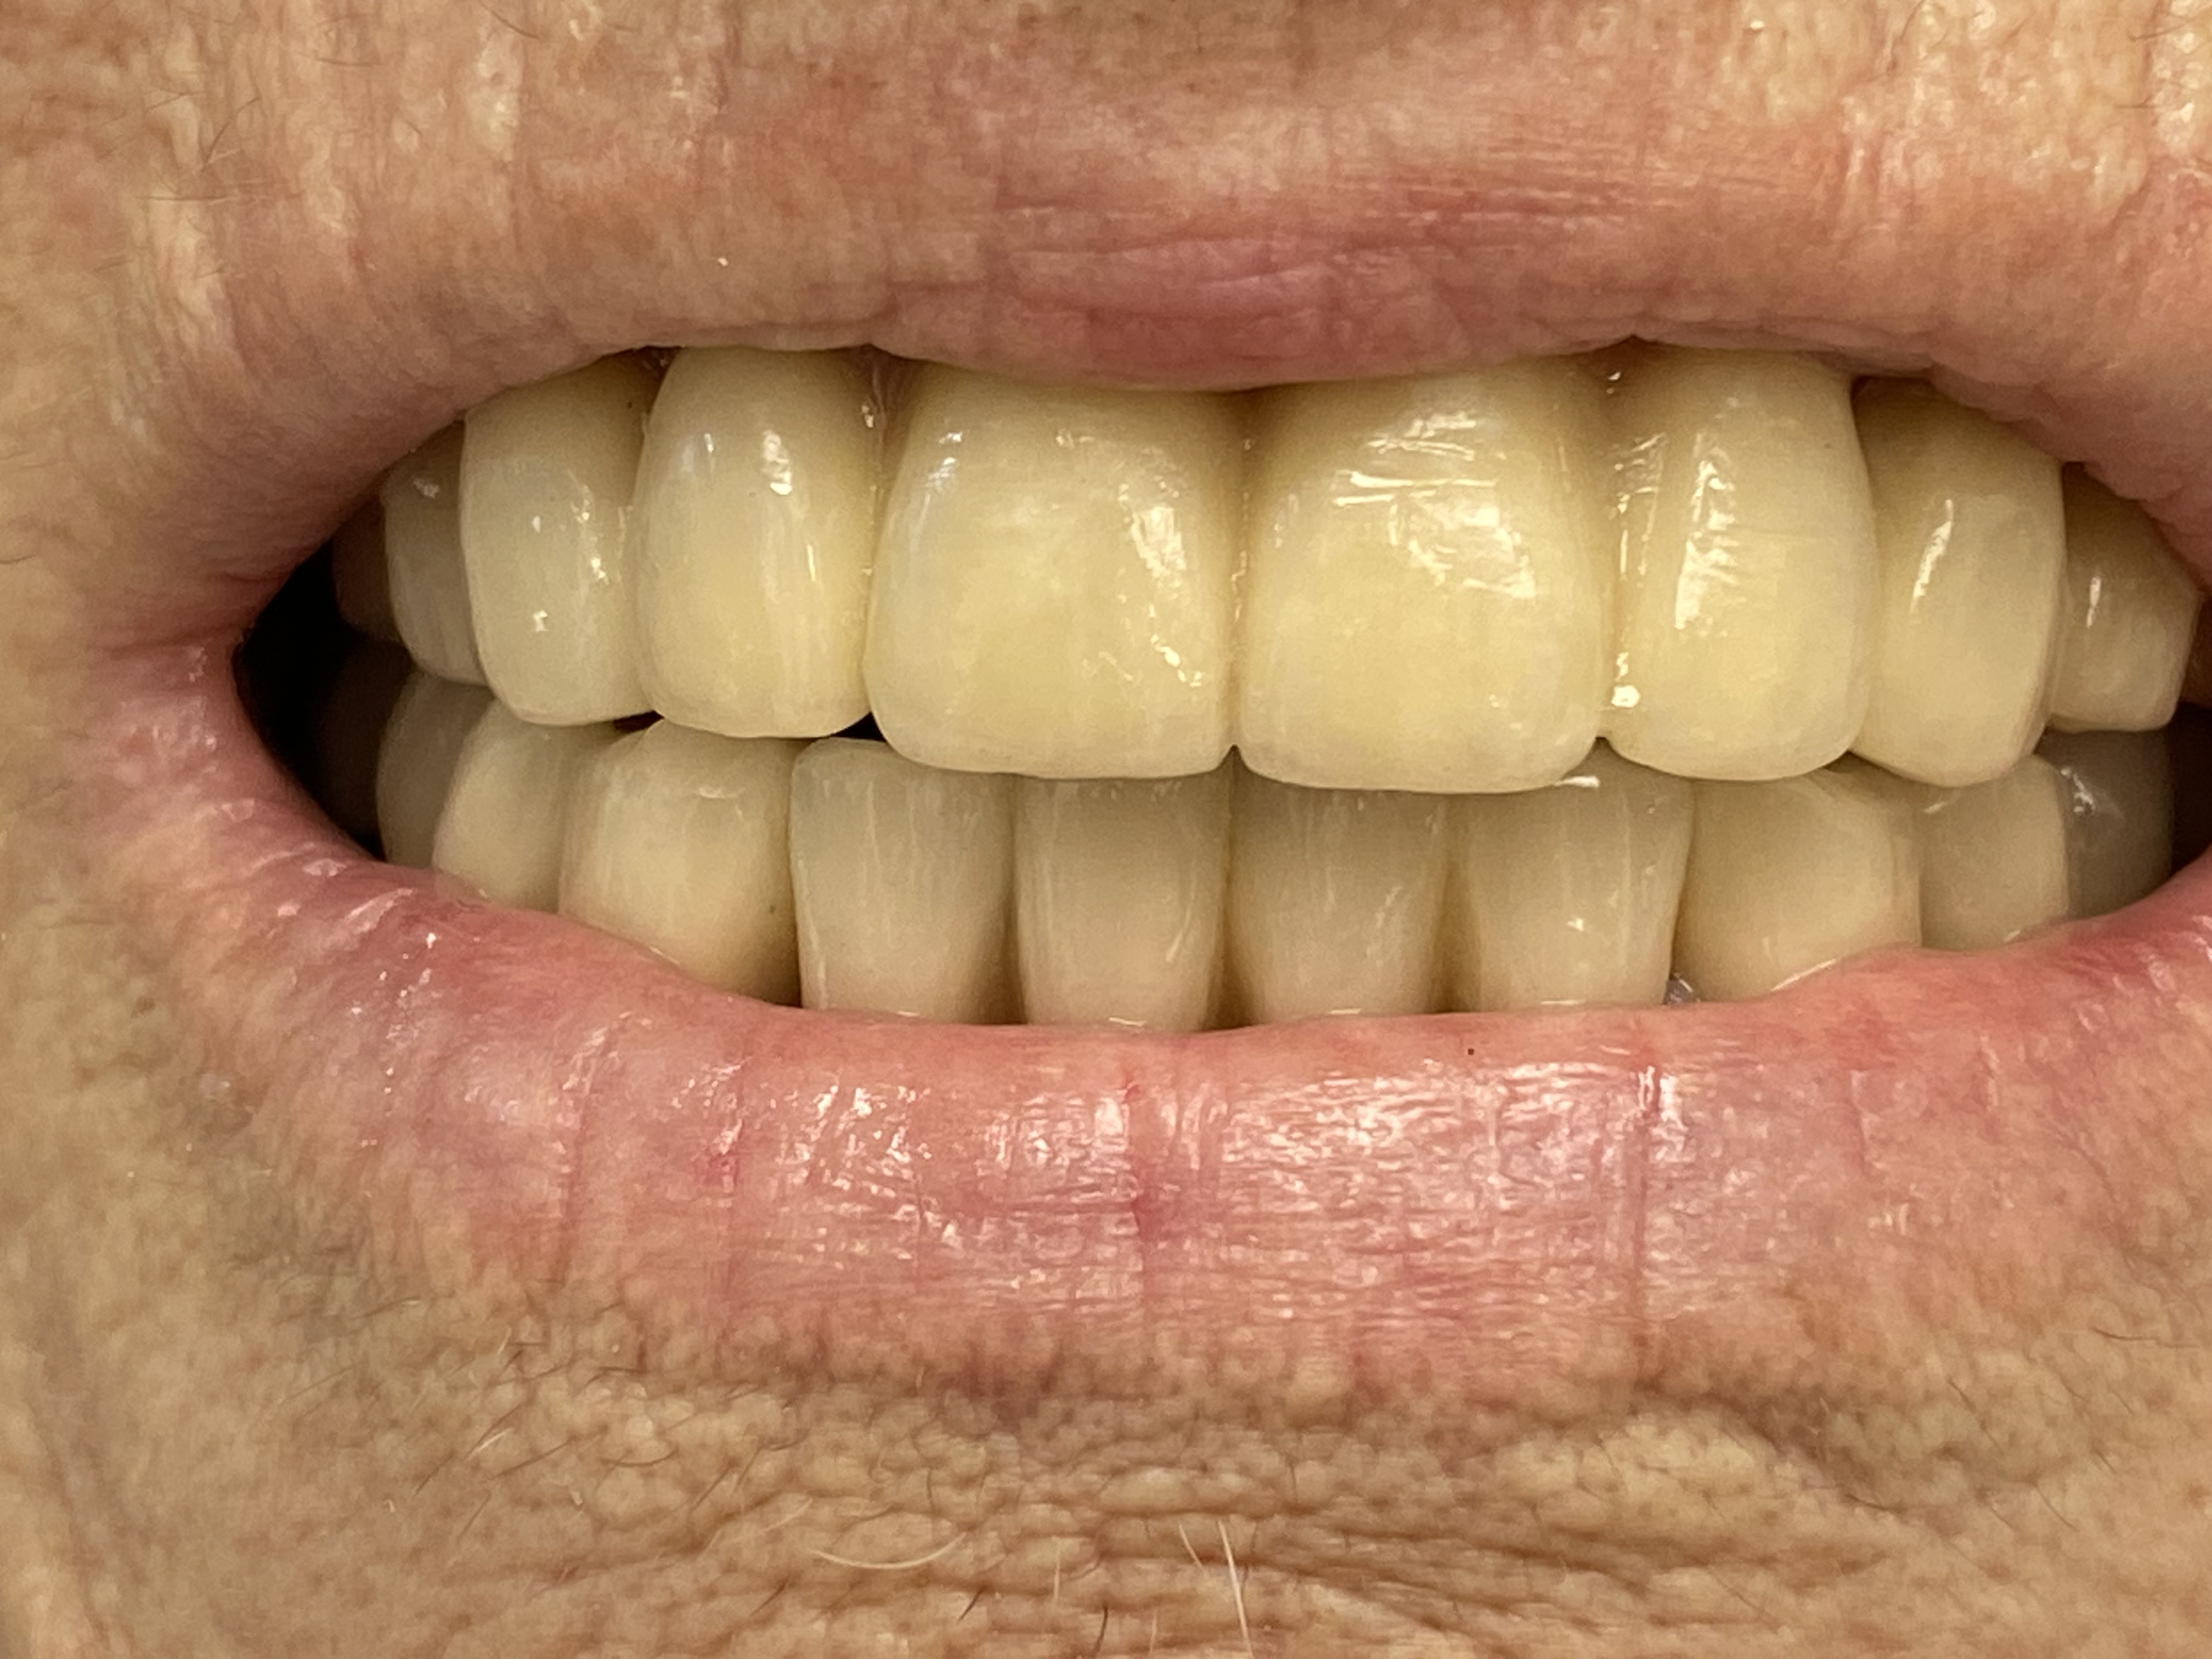

גשר הוא תותבת דנטלית קבועה בת מספר כתרים המחוברים כיחידה אחת , המשחזרת חוסר שן אחת או יותר על ידי חיבור שיניים טבעיות הסמוכות לאיזור חוסר שן-שיניים החסרות (עקב עקירה) משני צידי המרווח, או שתלים שיש ביניהם רווח הגדול מרוחב שן טבעית אחת או יותר